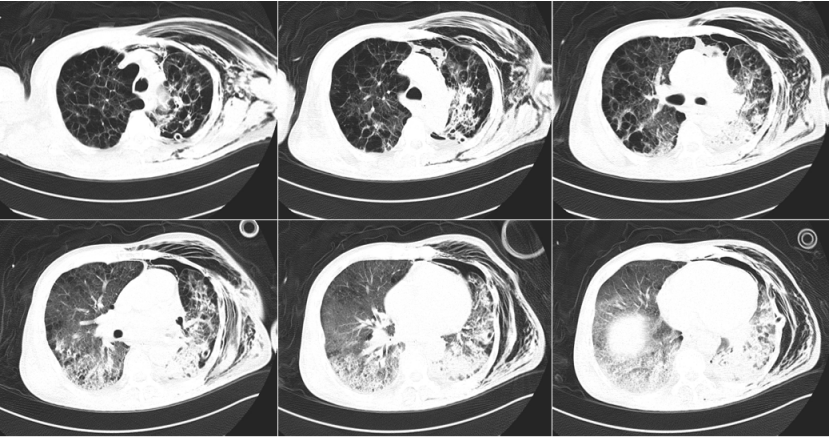

胸部增强CT(2023-11-18)

左肺下叶后基底段见肿块,大小约3.5 cm×4.8 cm,不均匀强化,考虑左肺下叶肺癌并左肺门淋巴结肿大,慢性支气管炎并双肺气肿(图1)

1  患者胸部CT(2023-11-18)

复查胸部CT(2024-02-16)

左肺下叶后基底段见肿块,大小约3.2 cm×4.7 cm,不均匀强化,双肺门淋巴结肿大较前片2024-01-16变化不明显,慢性支气管炎并感染,双肺气肿

2  复查胸部CT(2024-02-16)